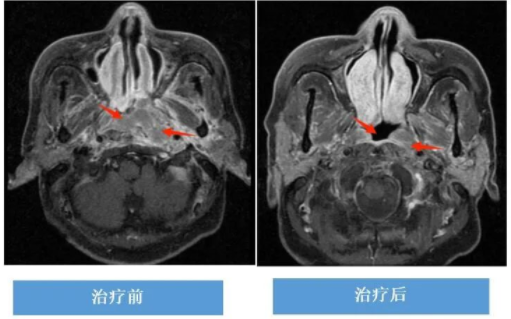

复发转移性鼻咽癌:免疫治疗+化学治疗